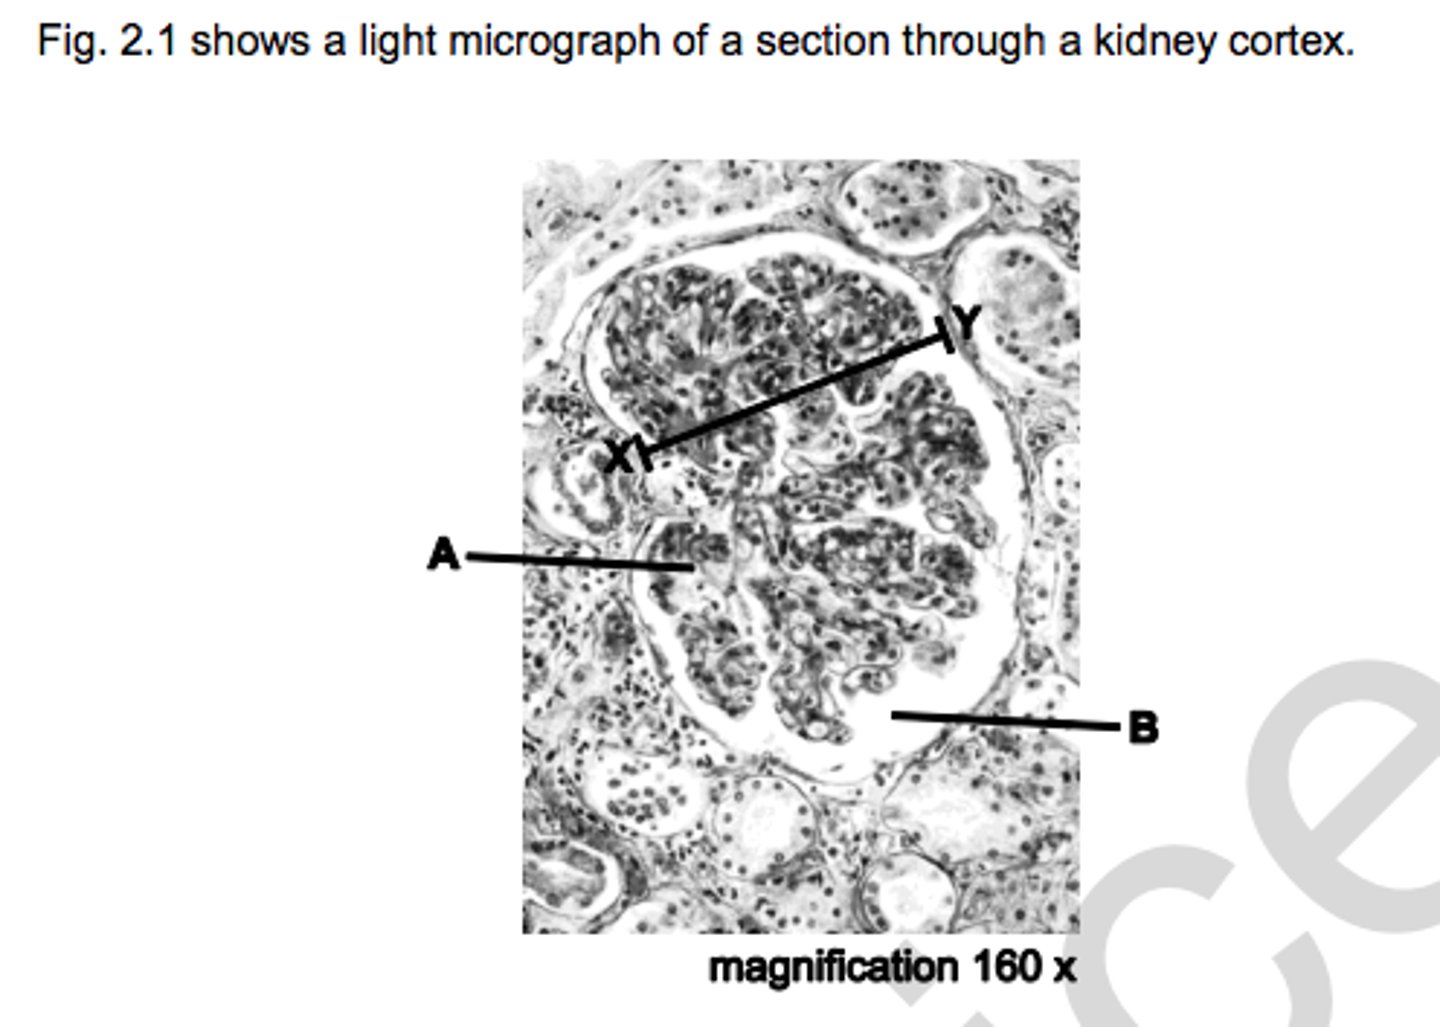

A - glomerulus

B - bowman's capsule

name A & B

A - bowmans capsule

B - glomeruli